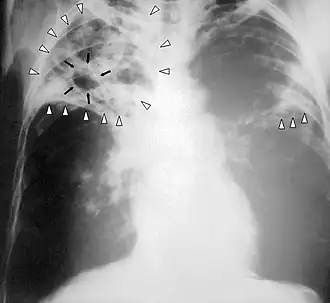

![]() Radiografie pulmonară (examen cu Raze X) a unei persoane bolnave de tuberculoză în stadiu avansat. Săgețile albe indică infecția în ambii plămâni. Săgețile negre arată cavitatea care s-a format. | |